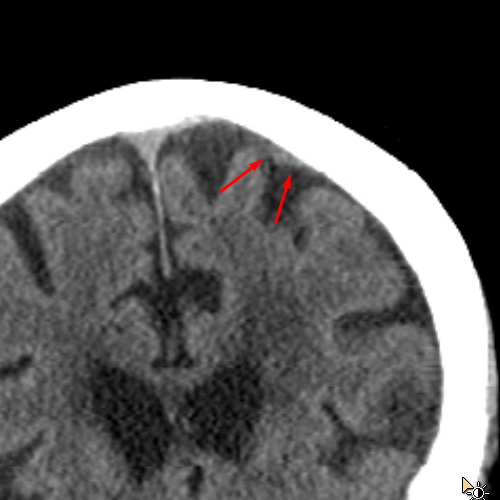

Age: 84

Sex: Female

Indication: Fall on anticoagulation